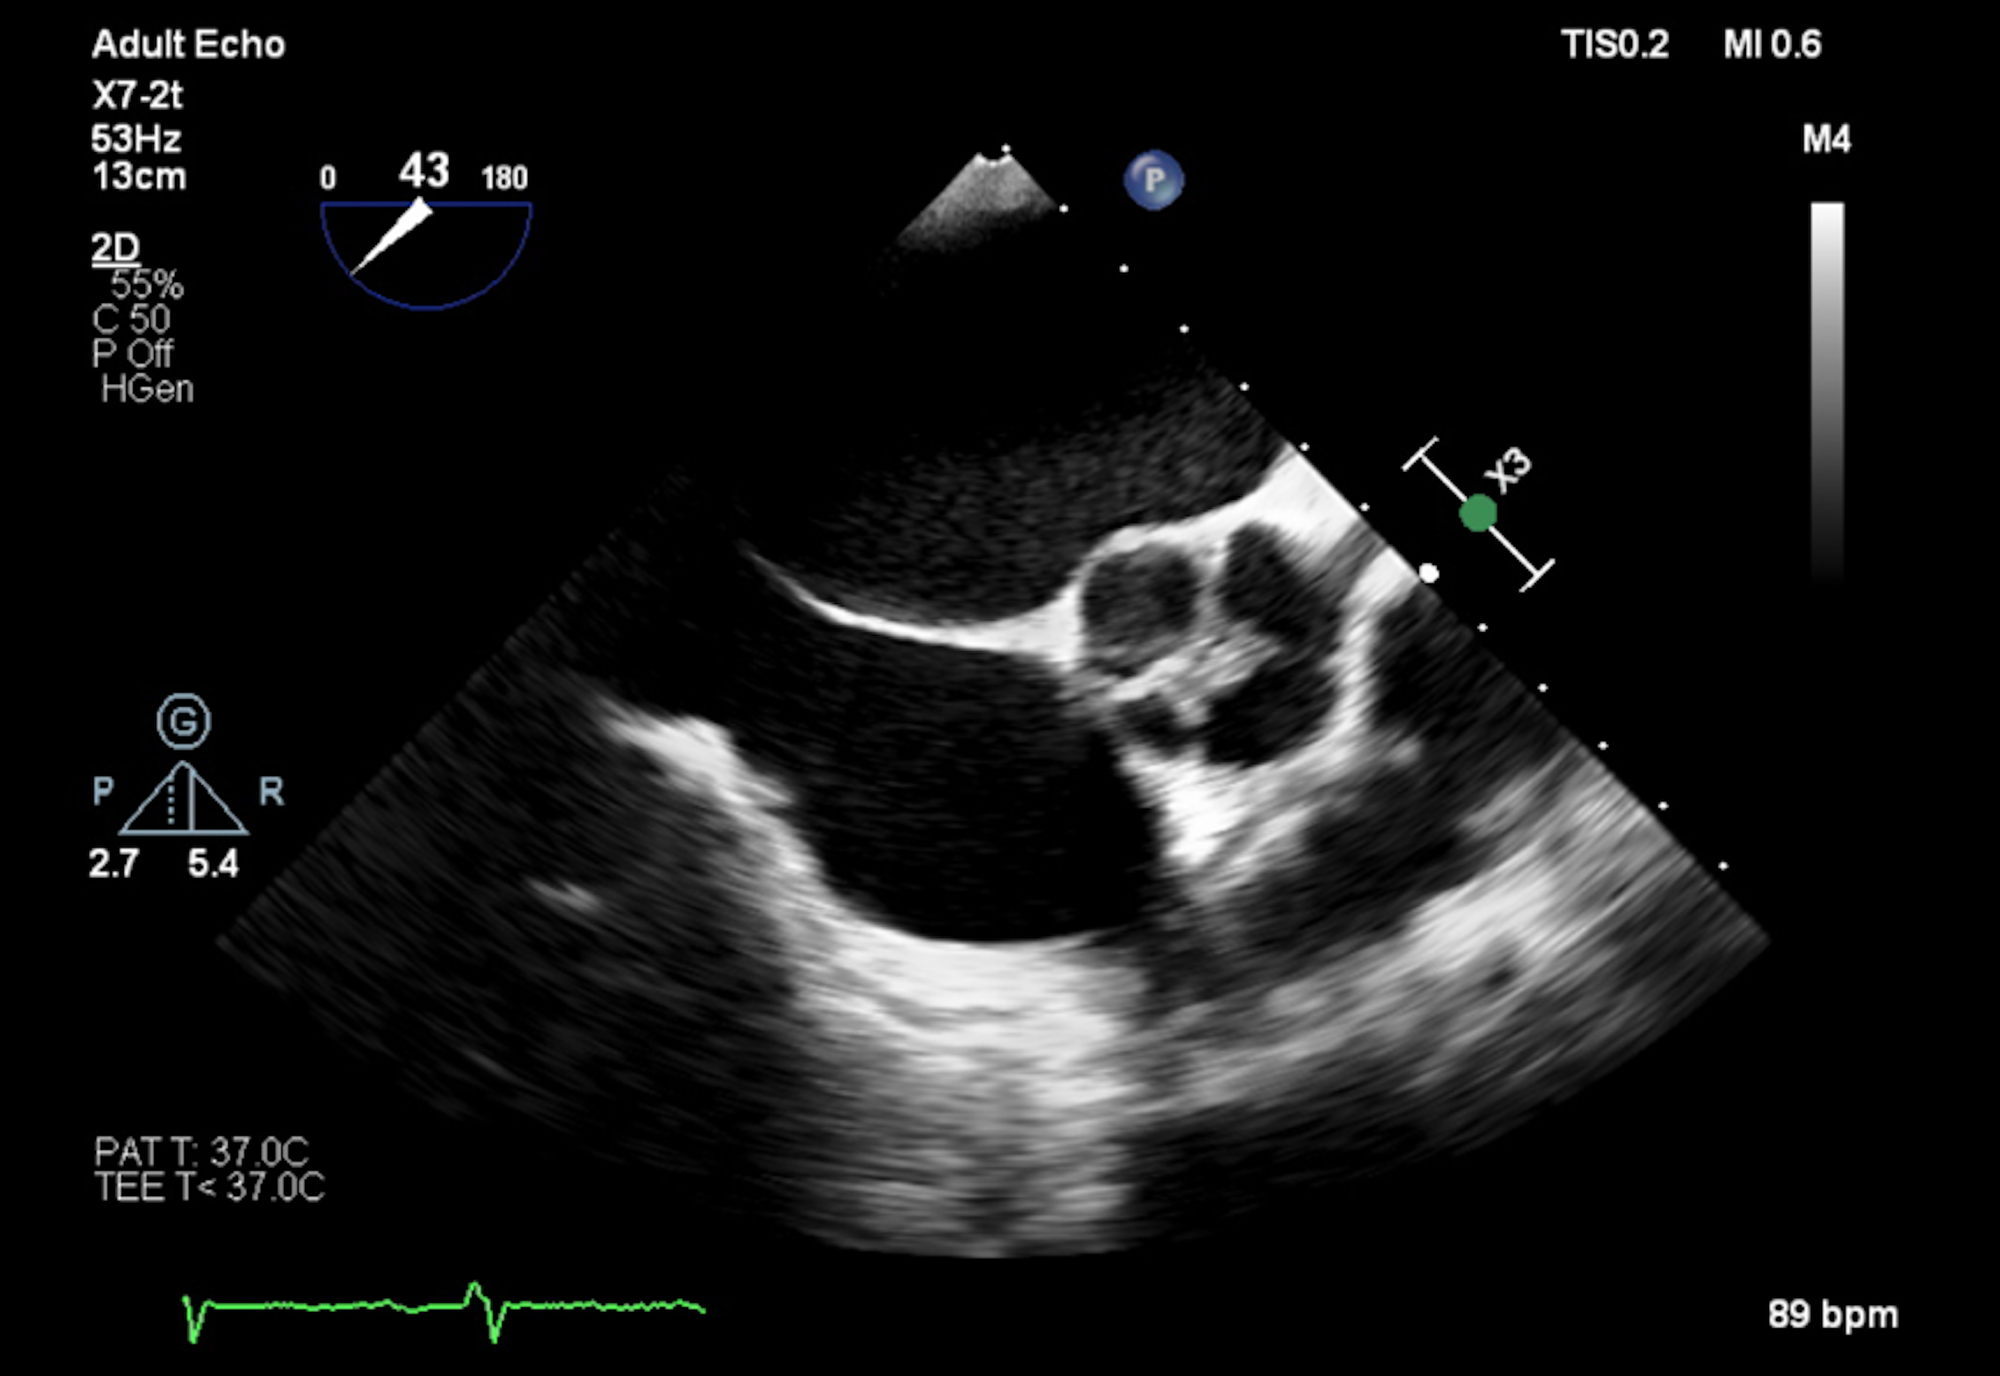

Vital signs were normal with a blood pressure of 113/74 mmHg, pulse rate of 60/min, temperature of 36.7 C, and respiratory rate of 15 breaths/min with normal oxygen saturation of 99% on room air. Physical examination revealed a grade 3/6 diastolic murmur in the aortic and mitral valve areas, with regular heart rhythm. Her lungs were clear to auscultation on both sides, and no pedal edema was present. The patient was noted to have a distended jugular venous pulse (JVP) with the nadir of the venous column on inspiration greater than 10 cm H2O. Electrocardiogram was significant for first-degree AV block, incomplete left bundle branch block, and T-wave inversion in leads aVL, V5, and V6. Troponins were repeated three times and were insignificant for ischemic disease. A TTE showed a severe reduction in left ventricular ejection fraction (15-20%). The patient was also found to have severe mitral and AR without any stenosis. There was no evidence of other significant valvular abnormalities. A subsequent TEE confirmed a quadricuspid aortic valve with three nearly identical cusps and one smaller cusp (Figure 1). CT angiogram of the chest showed a marginally dilated ascending aorta with a diameter of 4 cm.